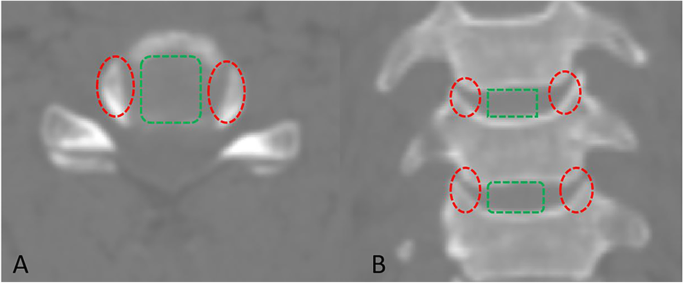

All solid foods were avoided for a minimum of 24 h but water was allowed before the operation. In addition, 1000 mg of cefazolin sodium was injected intravenously for perioperative prophylaxis. Each animal was positioned supine with the head and neck hyperextended after induction of general anesthesia. A longitudinal skin incision was carried out to reach the cervical spine through a standard right anterolateral approach. The longus colli was elevated bilaterally using an eletrotome for exposure at the C3–4 level. After confirmation of the segment, the C3–4 discectomy was performed, and then distraction was achieved with a Caspar distractor. A spinal curette combined with a high-speed drill was used for the preparation of the cartilaginous endplate of each vertebral body. The posterior longitudinal ligament was resected with a rongeurs and the decompression was made to reach bilateral uncovertebral joints. In Group A, an uncovertebral joint fusion cage of an appropriate size was implanted into the intervertebral space. A local autograft was grafted in the region of the bilateral uncovertebral joint, and two titanium screws were placed into C3 and C4 vertebrae respectively for initial stabilization of the cage; In Group B, an appropriate non-profile cage filled with a local autograft was implanted into the C3–4 disc space without bone grafting in the uncovertebral joint region, and two titanium screws were used for the initial stabilization of the cage (Fig. 4). The wound was irrigated and closed in a layer-by-layer fashion without drainage tube insertion. The goats were transferred to a metabolic cage for observation after extubation for the first week and then transferred to open pastures until the study was completed. Each goat received 1000 mg of cefazolin sodium intravenously per day for the first week. The goats were observed for 24 weeks and then sacrificed for a Micro-CT and histologic analysis after X-rays and CT scan examinations.

Anterior intraoperative view. The uncovertebral joint fusion cage (A) and the non-profile cage (B) were implanted at the C3–4 level using standard ACDF techniques: a local autograft (solid line box) was grafted in the uncovertebral joint region in Group A and no grafting (dashed box) was found in the uncovertebral joint region in Group B